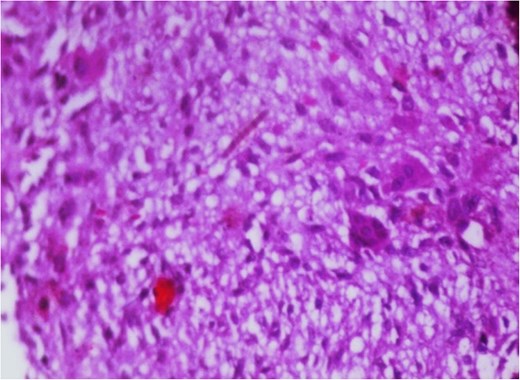

Additionally, magnetic resonance venography (MRV) confirmed a patent superior sagittal sinus with no encroachment of the lesion (Fig. 4). Differential diagnoses included dermoid cyst, eosinophilic granuloma, or benign fibro-osseous lesion. Surgical intervention involved en bloc excision under general anesthesia. A curvilinear incision was made over the mass, followed by subperiosteal dissection, which confirmed the lesion’s confinement to the diploë. Intraoperative frozen section analysis was not performed due to the lesion’s benign radiological features. Histopathological examination confirmed NOF, demonstrating ectodermal inclusion, cellular stroma of spindle-shaped fibroblasts arranged in a prominent storiform pattern, and scattered osteoclast-like giant cells. Notably, no evidence of mitotic figures, nuclear atypia, or necrosis was observed (Figs 5–7). The margins were free of lesional tissue. Postoperatively, the child resumed oral intake within 4 hours and was discharged on postoperative day 2 with analgesics. At the 6-month follow-up, the wound had healed without complications, with no recurrent lesion.

Photomicrograph in a case of NOF showing interlacing bundles of spindle-shaped fibroblasts in a storiform manner, H&E × 100.

Photomicrograph in a case of NOF showing interlacing bundles of spindle-shaped fibroblasts in a storiform manner, H&E × 400.

Photomicrograph in a case of NOF showing osteoclast-like giant cells, H&E original magnification × 400.